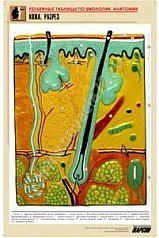

Комплект включает в себя 21 таблицу следующего содержания:

18. Кожа. Разрез;